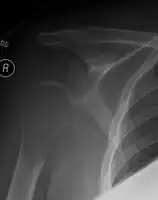

Solitary plasmacytoma in the long bone of the upper arm

The diagnosis of plasmacytoma uses a diverse range of interdisciplinary techniques including serum protein electrophoresis, bone marrow biopsy, urine analysis for Bence Jones protein and complete blood count, plain film radiography, MRI and PET-CT.[6][7]

Skeletal surveys are used to ensure there are no other primary tumors within the axial skeleton. MRI can be used to assess tumor status and may be advantageous in detecting primary tumors that are not detected by plain film radiography. PET-CT may also be beneficial in detecting extramedullary tumours in individuals diagnosed with SPB. CT imaging may be better than plain film radiography for assessing bone damage.[6][7]